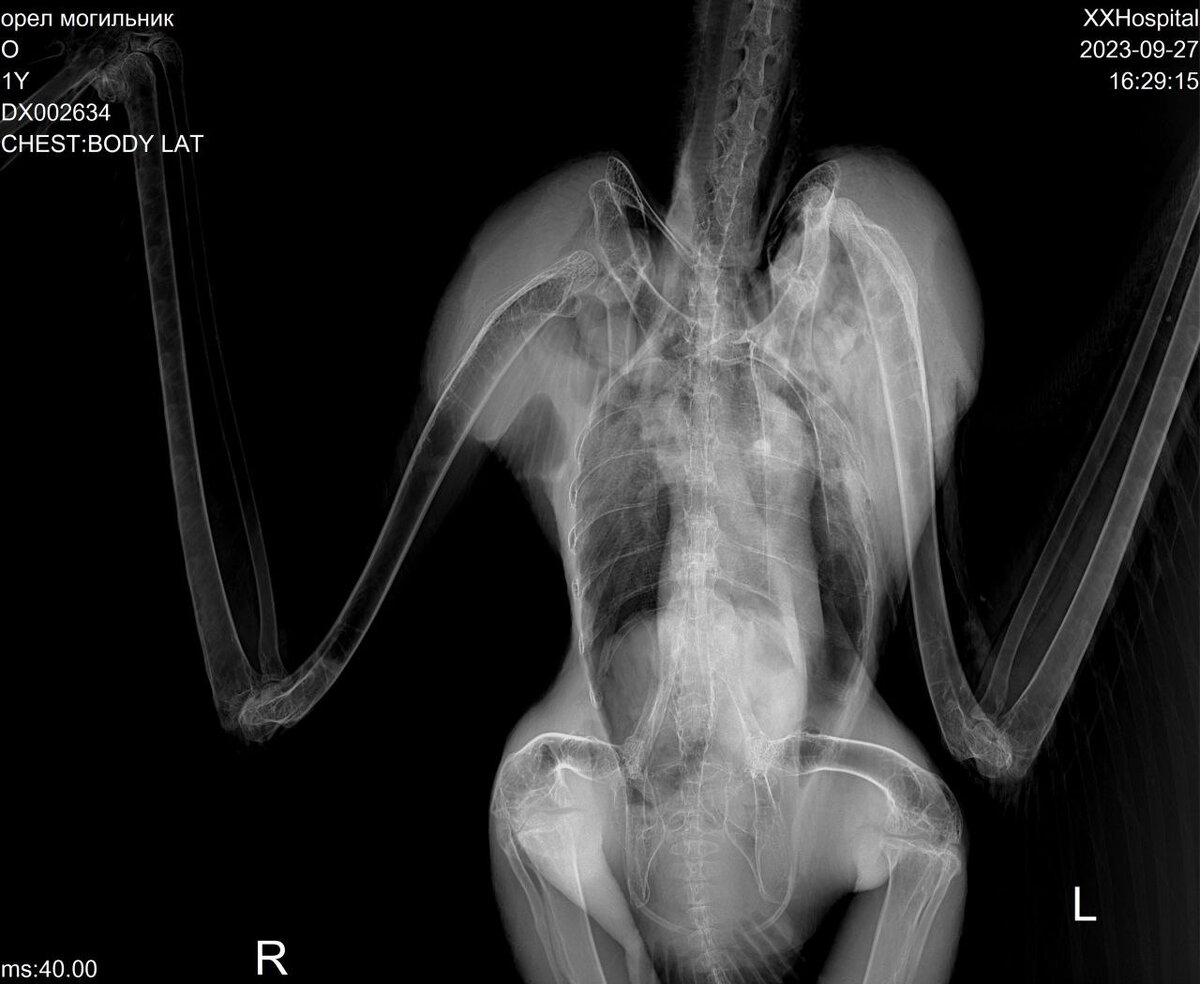

Волонтеры Севастьяновы сделали птице рентген. Оказалось, что у орла вывих плюс разрыв капсулы левого плечевого сустава. Такие травмы не операбельны, поэтому отпустить птицу после лечения в дикую природу не получится.

Также на приёме у врача удалось узнать, что это взрослая орлица. Она уже успела оставить после себя потомство. Весит она ровно 4 килограмма. Иксодовых клещей и пухопероедов в оперении птицы нет.